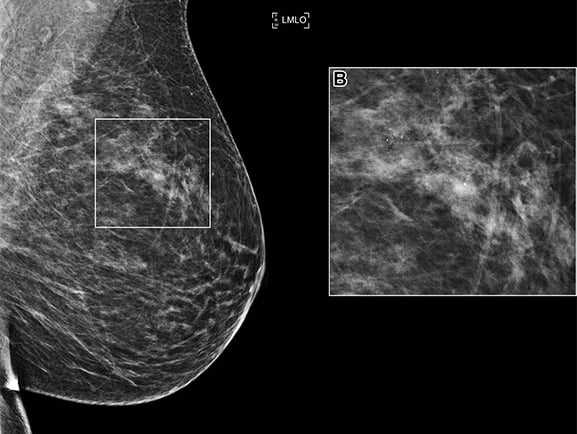

RSNA AI Challenge Models Can Independently Interpret Mammograms

Los algoritmos presentados para el Desafío de IA organizado por RSNA han demostrado un excelente desempeño para detectar cánceres de mama en imágenes de mamografía, aumentando la sensibilidad de detección y manteniendo bajas tasas de recuperación, según un estudio publicado en Radiology.